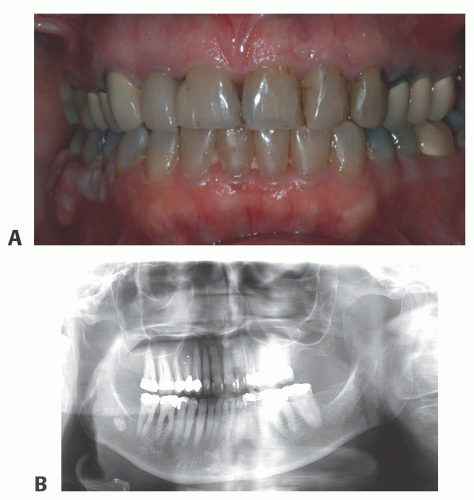

Along with clinical examination (FIG 1A), a panoramic radiograph (and selected dental radiographs, if necessary) examination is completed to assess the overall health and stability of the patient’s dentition.

When indicated, selected dental (periapical or bite-wing) radiographs are obtained (FIG 1B).